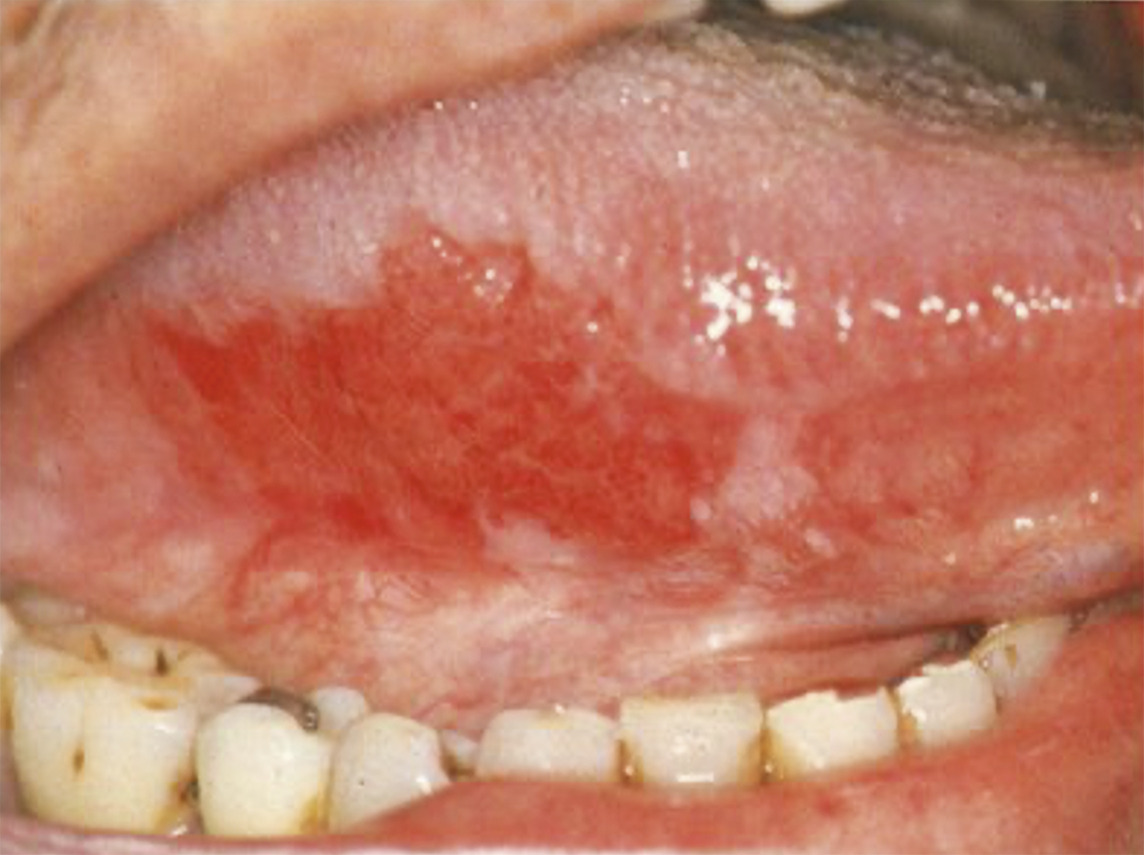

L’examen clinique de la cavité buccale dépiste des lésions précancéreuses telles que l’érythroplasie (fig. 5) ou la leucoplasie (fig. 6). Il recherche également la présence de lésions papillomateuses (fig. 7) évocatrices d’infection à HPV. Les lésions ulcérantes ou bourgeonnantes évoquent un cancer invasif (fig. 8) ; souvent douloureuses, elles peuvent s’accompagner d’une dysphagie, voire d’une limitation de l’ouverture buccale (trismus). On recherche une lésion ulcérante ou bourgeonnante de l’amygdale (fig. 9), de la base de la langue, du voile du palais ou de la paroi pharyngée postérieure. Il peut s’agir parfois d’une simple asymétrie.